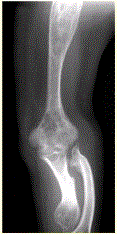

问题 患者男,22岁,长期存在骨和关节变形,近期出现右肘关节疼痛,进行性加重。行右肘关节X线正侧位片检查,见下图。 如患者无家族史,呈单侧发病,智力正常,则首选诊断为

选项 A.内生软骨瘤(Ollier病) B.遗传性多发性外生骨疣 C.神经纤维瘤病 D.进行性骨干发育不良 E.干骺发育不良 F.Albright综合征

答案 A